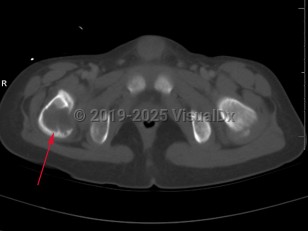

Eosinophilic granuloma of bone in Child

Langerhans cell histiocytosis (LCH) refers to a spectrum of diseases that includes eosinophilic granuloma (EG), Hand-Schuller-Christian disease, and Letterer-Siwe disease. EG is a rare (seen in 1-5 per million), benign tumor-like disorder that features clonal proliferation of Langerhans cells (antigen-presenting mononuclear cells of dendritic origin) usually found in bones; however, this can involve other organ systems. EG occurs most often in children aged 5-15 years, with a male-to-female ratio of 2:1. EG constitutes 60%-80% of cases of LCH and accounts for less than 1% of all bone tumors. Ninety percent of cases involve a single lesion, usually in the axial skeleton, with just under 10% of cases involving lesions in multiple bones or lesions in other organ systems (ie, skin, pituitary gland, gastrointestinal [GI] tract, lung, spleen, or brain).

The clinical presentation of EG depends largely on the location affected. EG is most often confined to the axial skeleton. EGs are often asymptomatic and found incidentally, or may initially present with pain and swelling of the affected area, with or without decreased range of motion. Commonly affected areas of the skeleton include (in order of frequency): skull, femur, pelvis, mandible, clavicle, ribs, and long bones (of the diaphysis and metaphysis).

Within the spine, EG accounts for 6.5%-25% of all spinal tumors, with the most common location being the thoracic spine, followed by the lumbar and then cervical spine. In cases of EG of the spine, the following symptoms have been reported: neck / back pain, limb weakness, neck / back stiffness with restriction of movements, kyphotic deformity, radiculopathy, and torticollis.